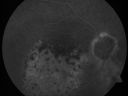

Pigmented Choroidal Mass Right Eye - Melanoma vs. Nevus vs. Unilateral Melanocytic Proliferation - 4 Month Follow-Up Images692 views71-year-old man his vision 4 month follow-up. Vision is 20/60 and patient sees flashing lights. Lesion has grown slightly in the superior half of the macula.     (0 votes)

Pigmented Choroidal Mass Right Eye - Melanoma vs. Nevus vs. Unilateral Melanocytic Proliferation - Initial Visit524 views71-year-old man is vision has been bothering him for about a month. He does not notice one eye particularly worse than the other. OD is 20/40, OS is 20/25 - Initial Visit     (0 votes)

Pigmented Choroidal Mass Right Eye - Melanoma vs. Nevus vs. Unilateral Melanocytic Proliferation - Initial Visit488 views71-year-old man is vision has been bothering him for about a month. He does not notice one eye particularly worse than the other. OD is 20/40, OS is 20/25 - Initial Visit     (0 votes)